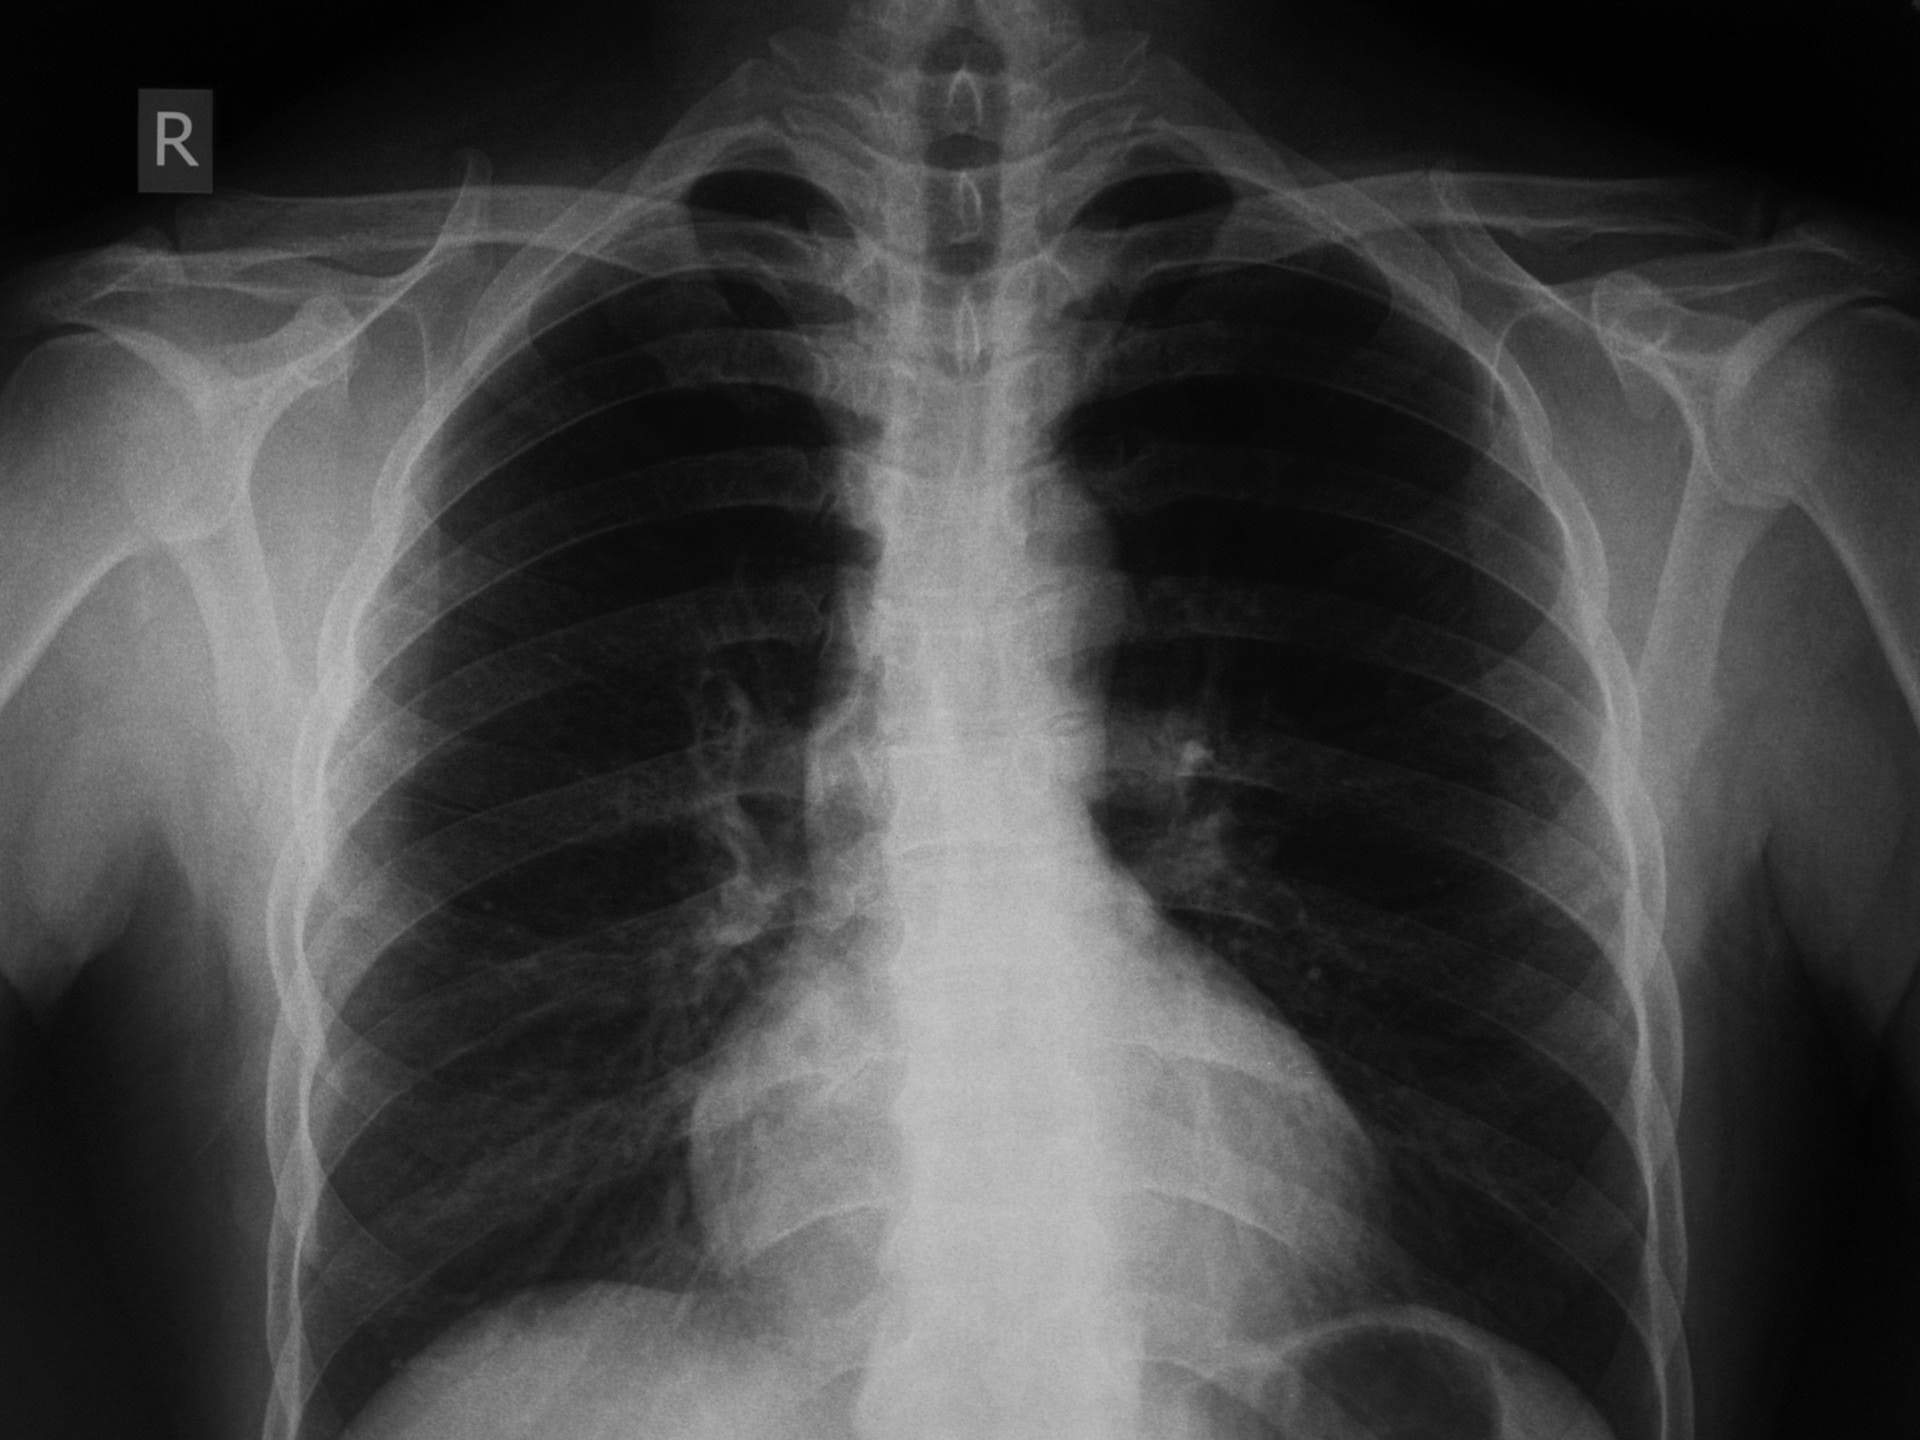

醫管局指,會按病人臨床需要決定是否需由放射科醫生閱讀X光影像。(資料圖片)

醫管局於11月21日公布三宗醫療失誤,分別來自威爾斯親王醫院、瑪麗醫院及瑪嘉烈醫院的醫護人員,未能適時察覺X光片顯示病人肺部出現異常陰影,三名病人其後確診患上肺癌,其中一名病人延誤醫治近三年,另外兩名病人則延誤診治達1.5年。醫管局當時宣布,在總辦事處層面成立根源分析委員會調查成因,及研究日後如何確保醫護不犯同類失誤。